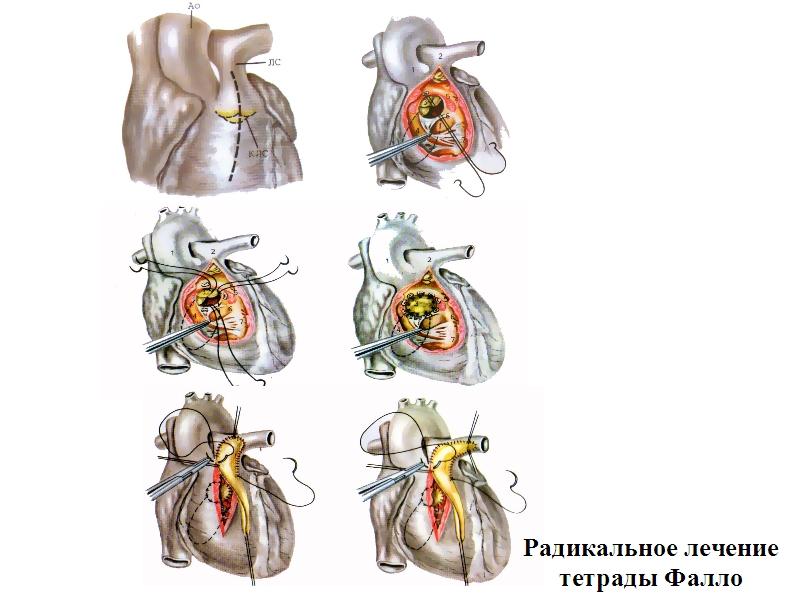

Фотографии и информация о приобретенных пороках сердца